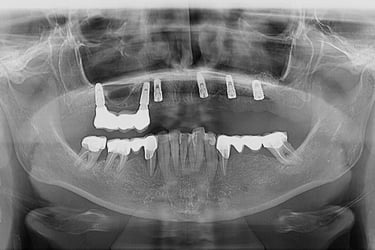

Se deceleaza imagistic o formatiune tumorala radiotransparenta, de mari dimensiuni, localizata la nivelul intregului grup frontal mandibular.

Dupa examenul clinic si imagistic se pune diagnosticul prezumtiv de formatiune tumorala chistica (chist radicular de mari dimensiuni). Se intervine chirurgical realizandu-se extractiile dintilor cauzali, irecuperabili, rezectii apicale a dintilor implicati chistic, care au fost tratati endodontic in prealabil. Piesa operatorie a fost trimisa catre examenul histopatologic, diagnosticul fiind chist radicular fara atipii.